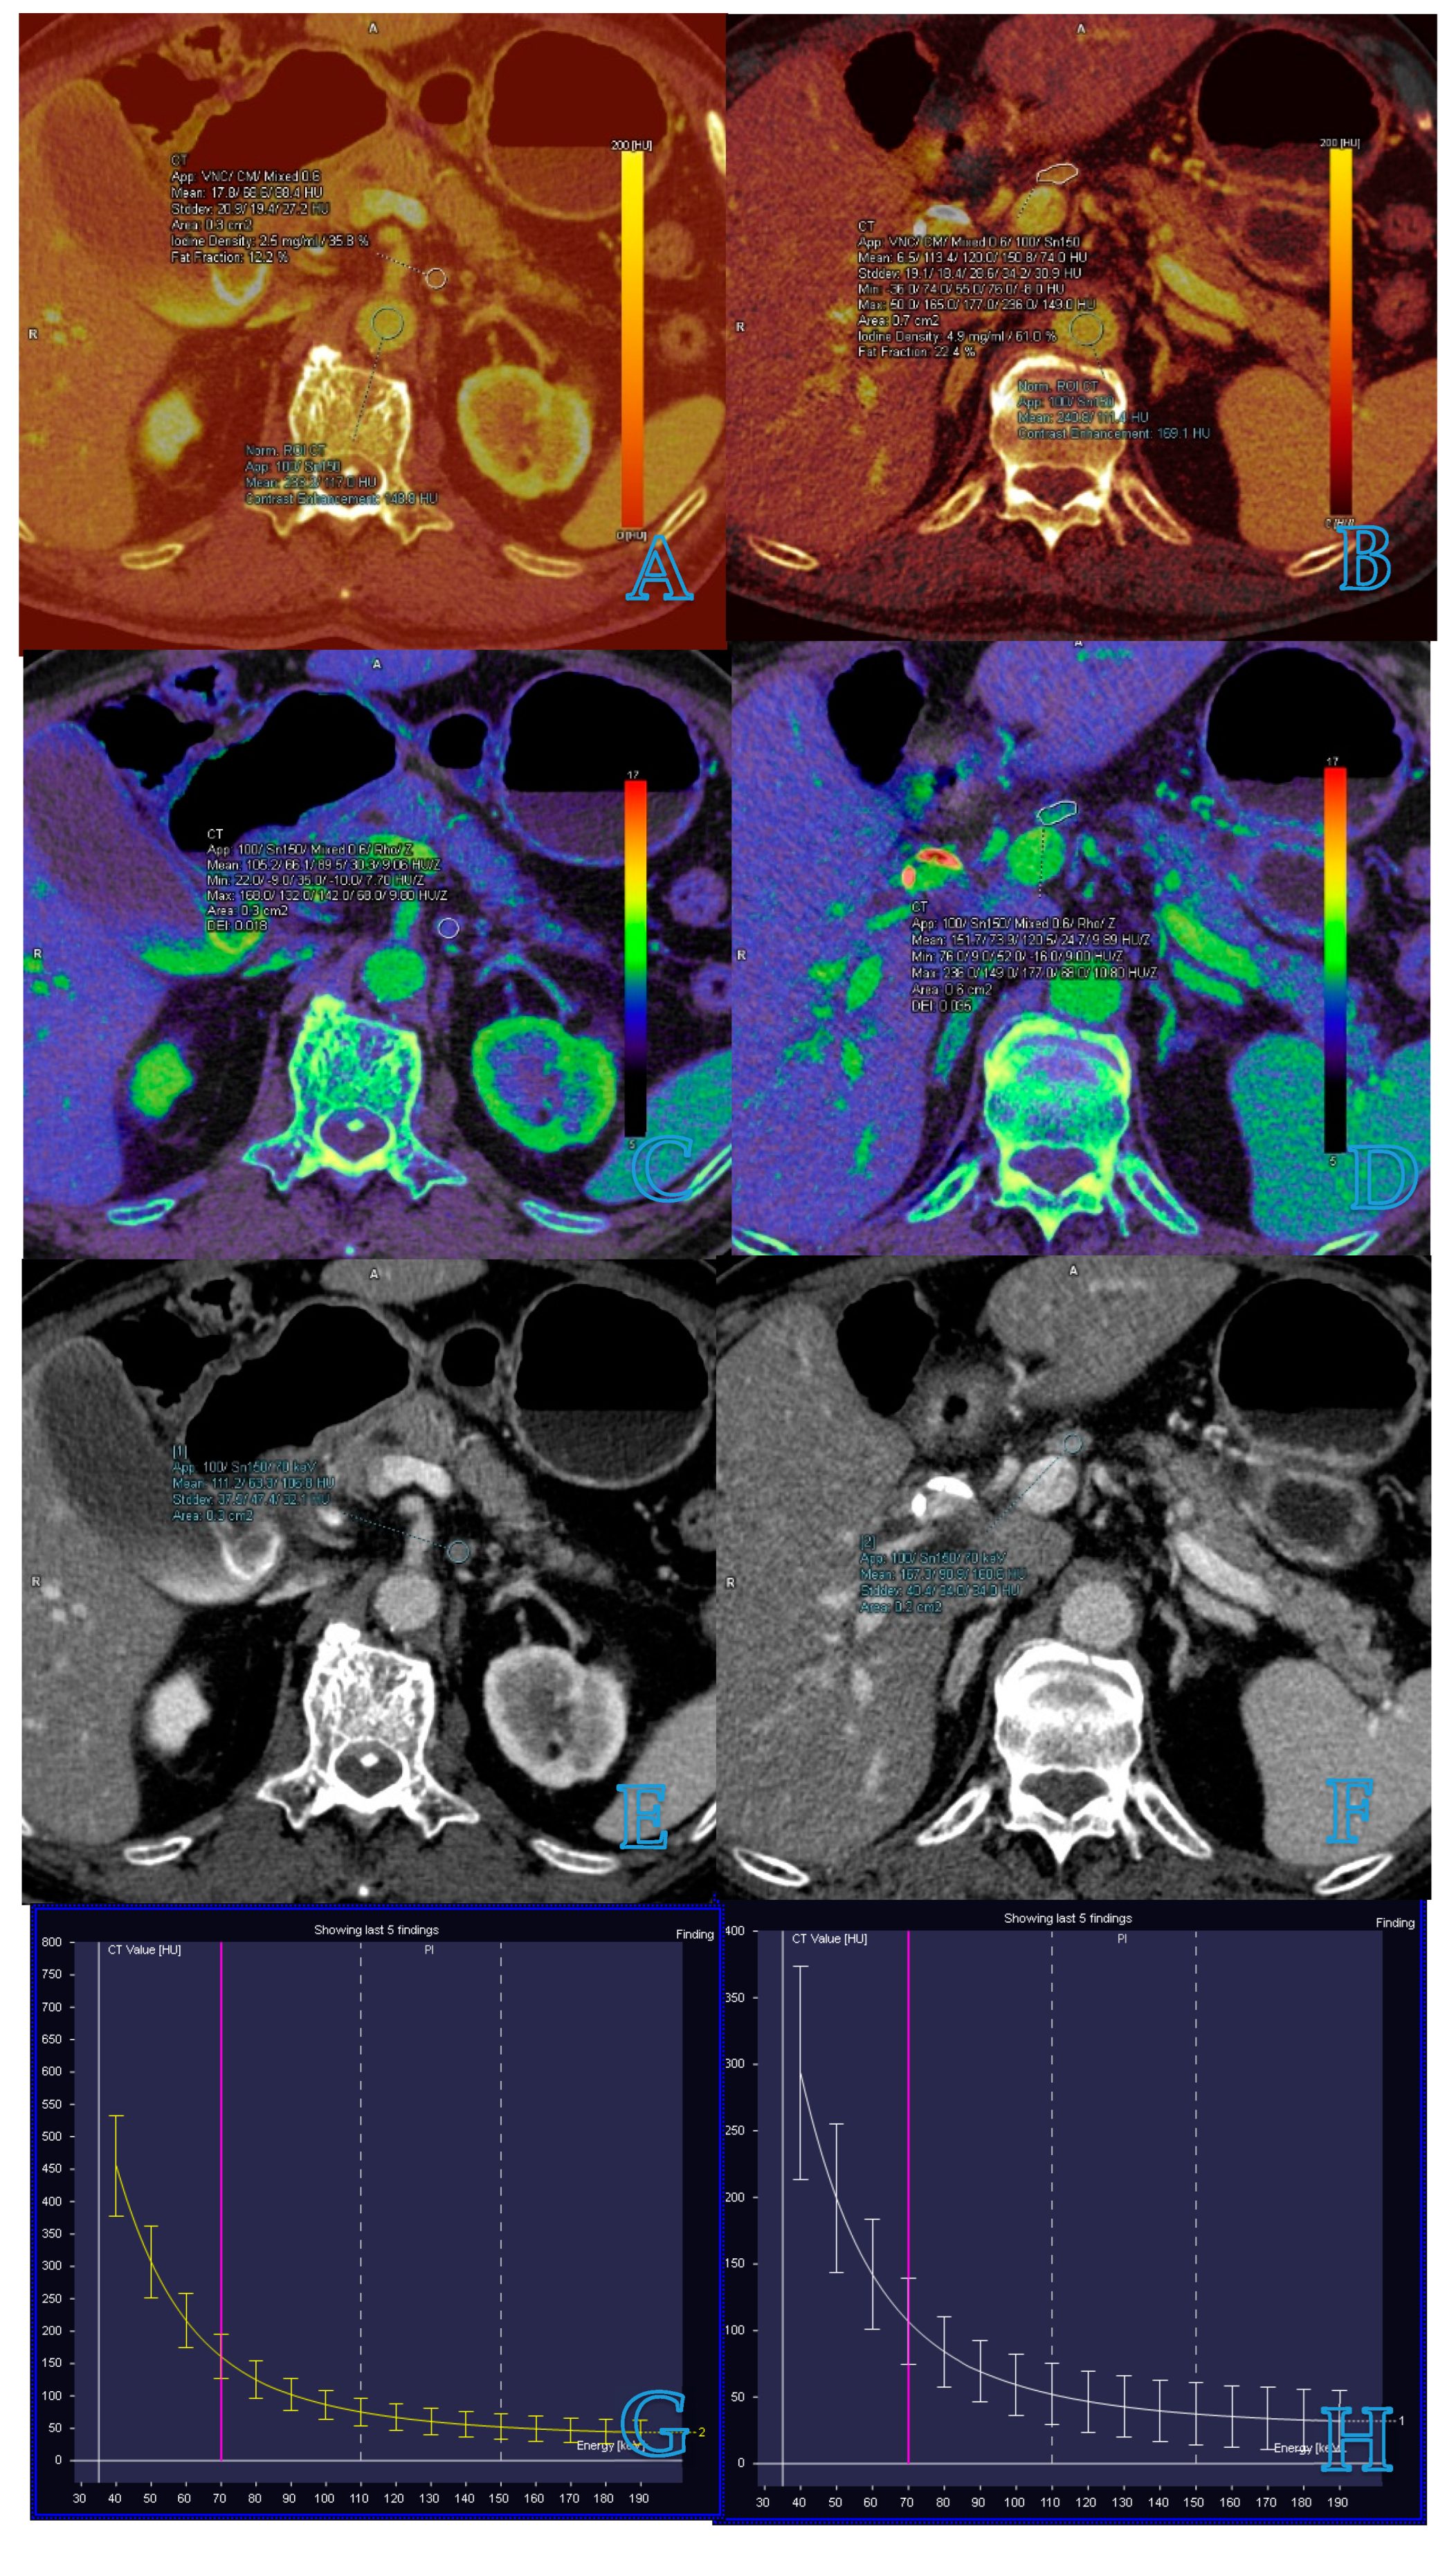

Iodine concentration (IC) and normalized iodine concentration (NIC) are parameters derived from iodine maps, which have been wildly used to detect LN metastasis in patients with malignant tumors (Figure 1A,B). Retrospective studies by Kato et al. and Liu et al. [10,22] have shown that IC and NIC are significantly lower in metastatic LNs than in non-metastatic ones, with IC in the portal venous phase (PP) being a particularly strong indicator. After excluding LNs with clear metastatic features identifiable through CT, Kato et al. [10] found that 5 of the remaining 50 LNs were indeed metastatic, with IC in PP remaining the most robust predictor for metastatic LNs (cutoff: 2.1 mg/mL, area under the curve = 0.933). Liu et al. [22] enhanced detection by combining NIC in PP with the short-axis diameter of LNs, which increased the overall accuracy to 82.9%. Furthermore, a meta-analysis by Kong et al. [15] evaluated the diagnostic accuracy of contrast-enhanced DECT for detecting metastatic LNs in patients with cancer. This study, which reviewed 16 studies encompassing 984 patients and 2577 LNs, revealed that NIC in the arterial phase, when used in conjunction with the arterial phase slope, significantly improved the identification of metastatic LNs, achieving a sensitivity of 94%, specificity of 74%, and an area under the curve (AUC) of 0.94.

Figure 1.

Measurement of dual-energy CT parameters for small lymph nodes in the same patient with pancreatic cancer. Images of benign lymph nodes are in the left column and images of malignant lymph nodes are in the right column. (A–D) Iodine concentration images and effective atomic number images, which outline the target lymph node and measure iodine concentration and effective atomic number. Venous phase contrast-enhanced dual-energy CT images show the target lymph node and λHU in non-metastatic and metastatic lymph nodes (E–H).

3.3. Spectral Hounsfield Unit Attenuation Curves

Spectral Hounsfield unit attenuation curves serve as a quantitative measure correlating with different energy levels in VMI. These curves represent the energy-dependent changes in attenuation within a region of interest, typically spanning from 40 to 140 keV [18]. Notably, the spectral Hounsfield unit curve varies across different tissues. The slope of the spectral Hounsfield unit curve (λHu) is particularly valuable for component analysis and differential diagnosis (Figure 1G,H). Recent studies have focused on λHu for detecting LN metastasis in patients with malignant tumors. A meta-analysis by Wang et al. [30] evaluated the utility of quantitative spectral CT parameters in identifying LN metastasis in lung cancer. Incorporating 11 studies with 1290 cases, the analysis revealed that the diagnostic performance of NIC and λHu in identifying lymphatic metastasis surpassed that of short-axis diameter, with a combined AUC exceeding 0.8. Yang et al. further demonstrated that DECT quantitative parameters offered greater accuracy than conventional CT morphological assessments [10]. Their retrospective study included 84 patients with lung cancer, evaluating a total of 144 LNs, of which 48 were metastatic. The study highlighted that when λHU was set at an optimal threshold of 2.75, the AUC in the diagnosis of metastatic LNs was 0.951, notably higher than the AUC of 0.780 achieved by conventional CT assessments based on size. Moreover, a prospective study by Zhang et al. [31] investigated the diagnostic performance of quantitative parameters derived from DECT for preoperatively identifying metastatic sentinel lymph nodes (SLNs) in patients with breast cancer. The study involved patients undergoing dual-phase contrast-agent-enhanced CT. The findings underscored that venous phase λHu was the most effective single parameter for the detection of metastatic SLNs, achieving an AUC of 0.88.